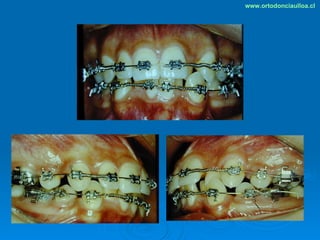

Este documento presenta dos casos clínicos de pacientes que recibieron tratamiento de ortodoncia. El primer caso fue de una paciente femenina de 14 años con apiñamiento dental y mordida cruzada que fue tratada mediante extracción de premolares y alineamiento dental. El segundo caso fue de un paciente masculino de 14 años con clase II esqueletal y desarmonía dentomaxilar que fue tratado con extracción de premolares y corrección de mordida. Ambos casos mostraron mejoría después de 3 años de tratamiento.